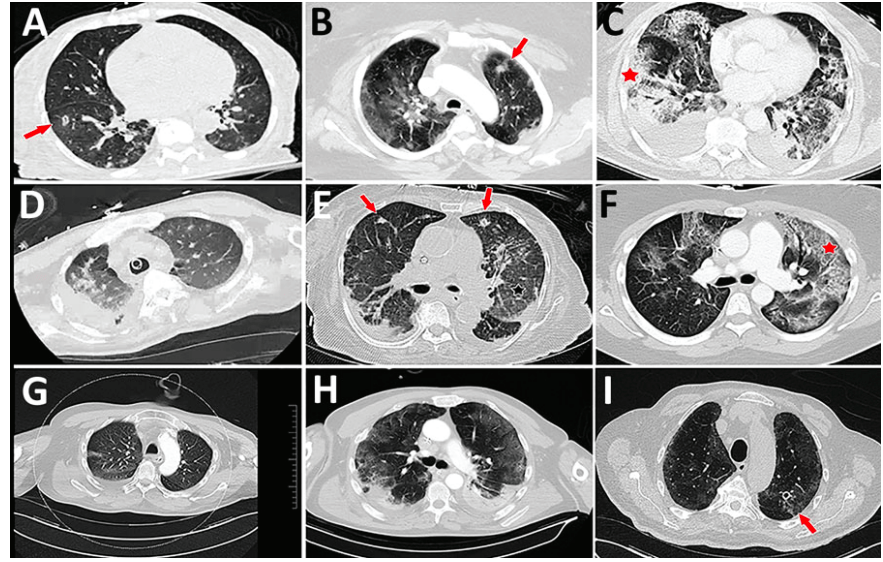

In cases for which CT scans were performed, radiographic reports generally described a mixture of findings attributable to the virus, findings consistent with airway inflammation and mucous, and radiographic findings consistent with airway-invasive disease (Figure 1).

Figure 1. Representative computed tomography (CT) scans for 9 patients with aspergillosis complicating severe viral pneumonia in patients with coronavirus disease. The nodules and cavitating nodules are indicated by red arrows, and prominent airway thickening and bronchiectasis in ground glass opacities are indicated by red stars.

Radiographic manifestations might be best understood when one considers that CAPA can be a constellation of mixed airway and invasive diseases.